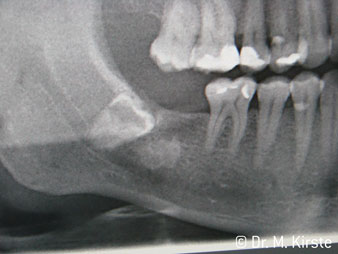

The 45° angle of the handpiece has been specially selected for its wide range of advantages. Colleagues who work in surgery, and for whom this handpiece was primarily developed, will soon appreciate the ability to work efficiently in very restricted spaces. In wisdom tooth extractions in particular (fig. 2) there is no need for large-scale spreading of the soft tissues in the cheek region (fig. 3). The design of the handpiece head combined with turning the head slightly during preparation allows work to be carried out quickly and safely in the retromolar region.